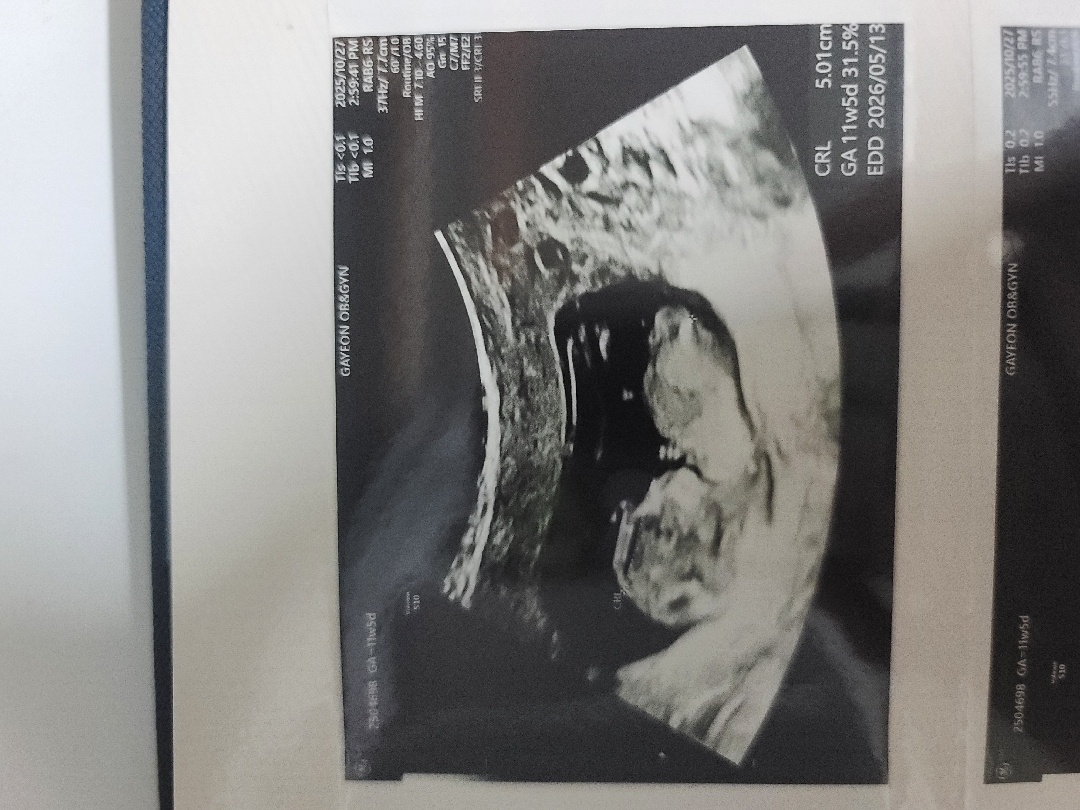

빌리는 60%로 딸이라는데 투표 해주세요

심소는 완전 아들같았거든요..헷갈려요